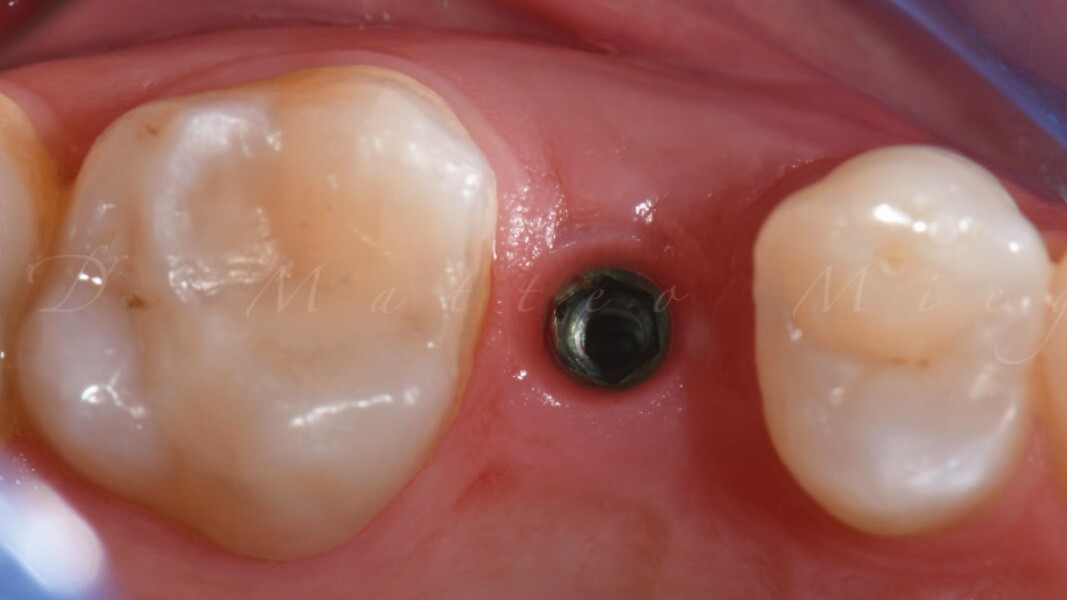

Una paziente di 50 anni presentava un premolare superiore non recuperabile. Dopo CBCT preoperatoria (T0) (Fig. 1), si è proceduto all’estrazione atraumatica e alla gestione dell’alveolo mediante posizionamento vestibolare di una membrana corticale eterologa (Lamina fine 0,7 mm, 35 × 15 mm, OsteoBiol) e riempimento con spugne di collagene (Figg. 2, 3). Sono stati applicati punti di sutura in nylon non riassorbibile 4/0. Dopo sei mesi di guarigione, una nuova CBCT (T1) ha consentito la valutazione della qualità ossea. Per la fase implantare è stato eseguito un lembo secondo la tecnica del roll flap, con preservazione delle papille interdentali e aumento del tessuto cheratinizzato (Fig. 4). È stato inserito un impianto JD Evolution Plus (4,3 × 11,5 mm) ottenendo un’eccellente stabilità primaria. Durante la chirurgia è stato prelevato un campione osseo per analisi istologica (Fig. 5).  Il lembo è stato suturato con nylon 4/0 intorno all’abutment di guarigione. Dopo due mesi, la paziente è stata riabilitata con una corona monolitica in zirconia realizzata da impronta digitale intraorale (Fig. 6).

L’esame istologico ha confermato la presenza di osso neoformato mineralizzato con buona integrazione del materiale eterologo residuo. L’inserimento implantare è risultato stabile e privo di complicanze (Figg. 7-12).